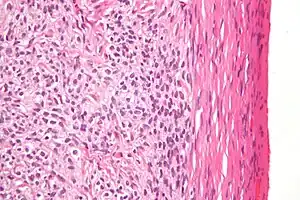

| High magnification micrograph of a thecoma. H&E stain. | |

Low magnification micrograph of a thecoma showing compression of the ovarian cortex (right of image). H&E stain.

Grossly, the tumour is solid and yellow.

Microscopically, the tumour cells have abundant lipid-filled cytoplasm.